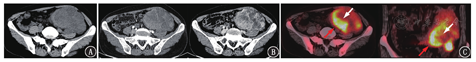

患者女,55岁,因"大便困难伴里急后重4 d"入院。患者于4 d前出现排便困难,伴大便变细,偶不成形,无血便,无畏寒、发热等症状。体格检查:左下腹触及大小约5 cm×5 cm肿块,质硬,无法推动,无压痛。实验室检查(括号内为正常参考值范围):WBC计数17.1(3.3~9.5)×109/L,C反应蛋白70.9(0~5.0) mg/L,糖类抗原(carbohydrate antigen, CA)125 68.3(0~35.0) kU/L。全腹部CT平扫+增强(图1A,图1B)示:左侧中下腹腔见一巨大不规则形富含黏液的混杂密度肿块,边界欠清,伴有分叶,大小约8.1 cm×8.3 cm×11.7 cm,与乙状结肠分界不清,邻近乙状结肠受压,左侧卵巢显示不清;增强扫描动脉期肿块呈结节状、条片状强化,静脉期及平衡期强化面积扩大、强化程度增高,呈渐进性填充强化。

为明确病变性质,患者行18F-脱氧葡萄糖(fluorodeoxyglucose, FDG)PET/CT(美国GE Discovery STE)显像(图1C)示:肿块实性部分18F-FDG摄取明显增高,最大标准摄取值(maximum standardized uptake value, SUVmax)为16.8,间质部分摄取相对不高,SUVmax为4.0,考虑乙状结肠间质瘤。电子结肠镜检查:进镜20 cm可见一巨大黏膜隆起,表面粗糙,活组织检查弹性可,致肠腔稍狭窄。肿块切除术术中乙状结肠见一浸润性肿块,大小约10 cm×15 cm,明显浸出浆膜层,侵犯左侧腹壁。大体检查:送检肠管1段,肠管长18 cm,周径6~9 cm,黏膜表面尚光滑,距切端3 cm乙状结肠见一巨大团块状肿物,大小约14 cm×7 cm×6 cm,位于黏膜下至浆膜外,切面灰白色,质韧,局灶出血,见暗红色。病理检查(图2):光学显微镜下示肠壁间及浆膜面见肿瘤细胞弥漫片状分布,部分漂浮于黏液间质中。瘤细胞形态卵圆形,部分呈上皮样。胞质丰富、嗜双色,核大,空泡样,核仁及核分裂象易见。间质中大量炎性细胞浸润,以中性粒细胞为主。免疫组织化学检查示:间变性淋巴瘤激酶(anaplastic lymphoma kinase, ALK)(P80)(+++)、ALK(D5F3)(+++)、结蛋白(desmin;+)、CD30(+)、细胞增殖核抗原Ki-67(30%)、CD34(血管+)、平滑肌肌动蛋白(smooth muscle actin, SMA;-)。最终诊断:乙状结肠上皮样炎性肌纤维母细胞肉瘤(epithelioid inflammatory myofibroblastic sarcoma, EIMS)。

EIMS富含黏液样基质,并有大量炎性细胞浸润,可分为单发肿块型、多发结节型、弥漫浸润型及混合型[3]。本例表现为盆腔孤立性巨大肿块,位于乙状结肠黏膜下,侵及肠道肌层、浆膜层。该肿瘤富含大量黏液样基质,CT平扫常呈现整体密度相对较低的混杂密度,增强扫描肿瘤实质细胞早期即明显强化,延迟期持续强化,在间质区延迟强化或不强化,导致肿瘤在延迟显像时强化面积逐渐扩大、强化程度逐渐增加,呈"快进慢出"的强化特点。本例病灶18F-FDG摄取明显增高,但均匀性较低,病灶内存在较多放射性缺损,同时可见全身骨髓和脾有较明显的反应性增生。Dong等[4]的研究表明,IMT 18F-FDG摄取高低与肿瘤细胞结构、生物学行为以及炎性细胞的组成比例、激活程度相关,而EIMS是一种恶性IMT,所以呈高摄取表现。病灶对18F-FDG高摄取的原因除肿瘤细胞增殖活跃外,还与炎性细胞对18F-FDG的高摄取有关,而间质部分以黏液为主,导致18F-FDG摄取相对不高。本例患者外周血WBC计数明显增高,与病理所见的肿瘤内大量炎性细胞浸润和PET所见的骨髓、脾代谢弥漫性增高有密切关系[5]。